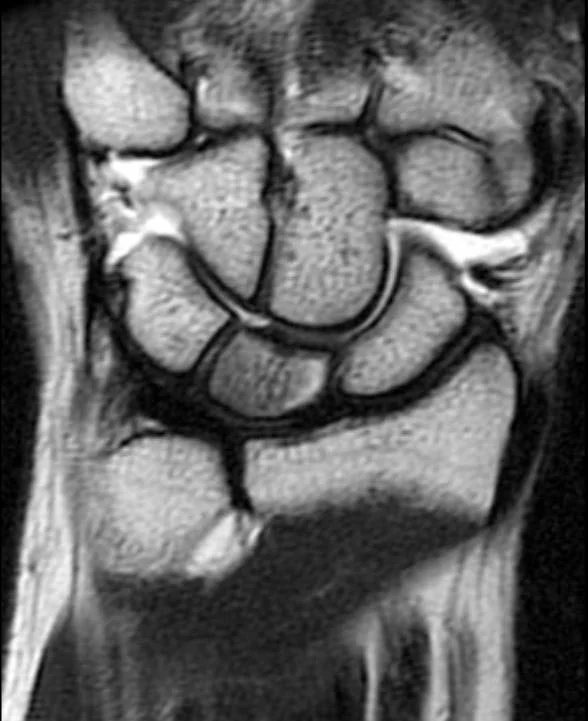

• Avascular necrosis of the lunate

• XR = sclerosis and flattening of lunate

• MRI = best test

• Sclerosis centrally (low T1 & T2)

• May see edema in acute phase